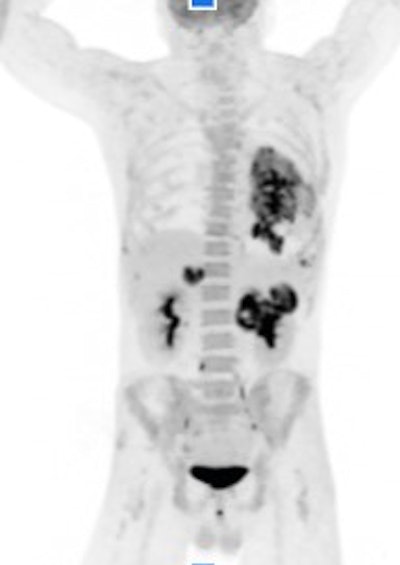

The main highlight in the molecular imaging area of Canon's virtual booth is Cartesion Prime, a digital PET/CT scanner. Canon is touting the fact that the system is 100% air-cooled, and it's now available in an option with a 160-slice CT scanner, adding to the 40-slice and 80-slice configurations that were previously offered.

Canon is highlighting AiCE DLR reconstruction for Cartesion Prime for both the CT and PET components, and the company is showing PET/CT images acquired in 2.5 minutes, at 30 seconds over five bed positions.